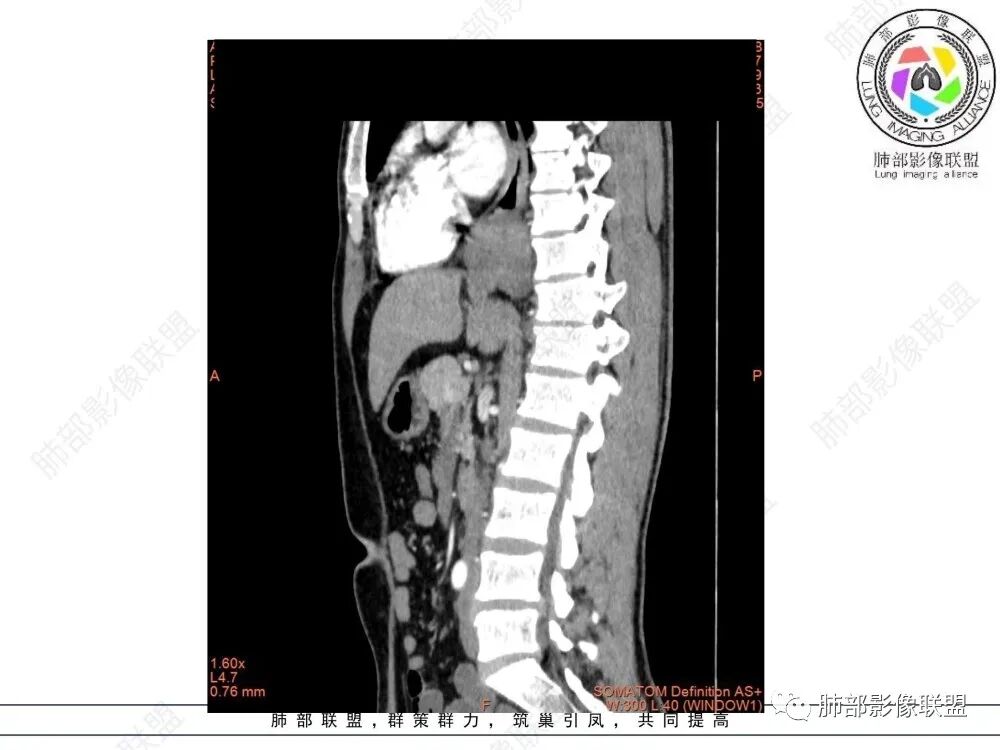

食管平滑肌瘤是最常见的食管良性肿瘤,多见于男性,男女之比为2.6:1,高发年龄 30~60岁之间与食管癌相比,食管平滑肌瘤 的一个主要特点是病史相对较长,病情进展缓慢。病史最长者达10年余,平均 15.7个月,尽管病史较长,但大多数患者仍能进普食。食管平滑肌瘤的诊断一般比较容易,结合患者临床症状、食管造影及食管镜所见,一般均能得出正确诊断。食管造影主要为充盈缺损,病变与食管壁成锐角,粘膜线连续无破坏,管腔收缩扩张比较自如。钡餐造影敏感性高,但对食管壁间及食管周围情况难以判断。CT具有极高的密度分辨率,并且可以获得高质量的多平面重组图像,有利于食管壁间及食管周围情况的判断,表现为食管下段环绕管壁生长,偏心性或薄厚不均软组织密度肿块,密度均匀,内缘分叶状,管腔与正常食管壁构成不规则多角形扩张,增强动脉期无强化,多角度重建其病灶长轴与食管长轴不一致。由于食管壁在收缩状态下厚度约为5.6mm,扩张状态厚度不超过3mm,CT扫描时保持食管处于扩张状态可提高小病灶检出率。MR表现为T1加权等信号,T2加权稍高信号,可见高信号粘膜层,增强扫描轻度渐进性强化,密度均匀,无出血坏死。对于粘膜及周围脂肪间隙的判断具有明显优势。